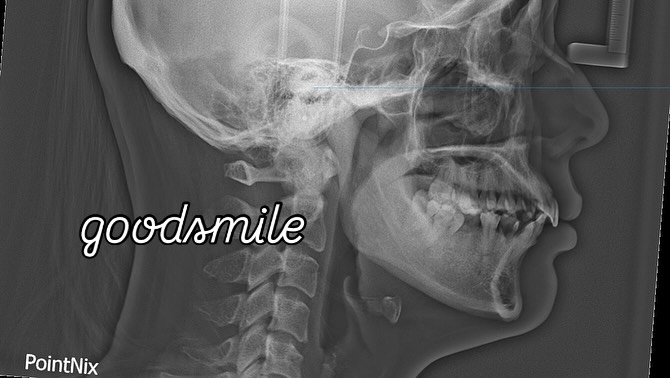

molar protraction

non ext

lip protrusion